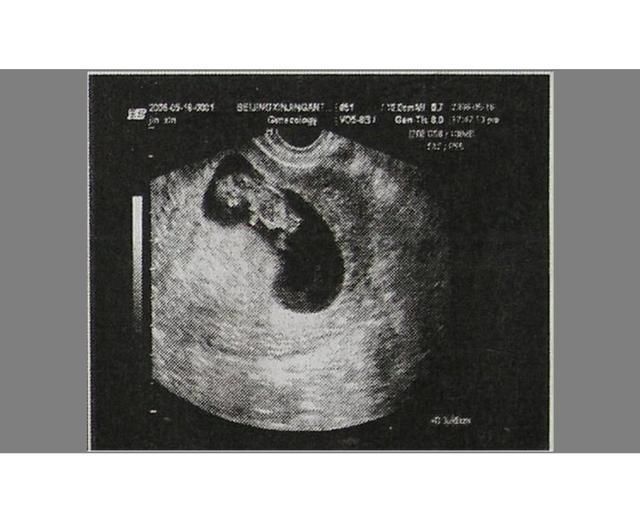

孕早期胚胎发育过程胎儿在孕妈肚子里的早期发育过程是这样的:

0到4周时属于胚前期,5到10周属于胚胎期,11到40周属于胎儿期。

- 30到40天形成胎囊;

- 40到50天形成胎芽;

- 50-60天形成胎心;

一般在42天左右去医院做个B超检查,可以看到完整的孕囊。